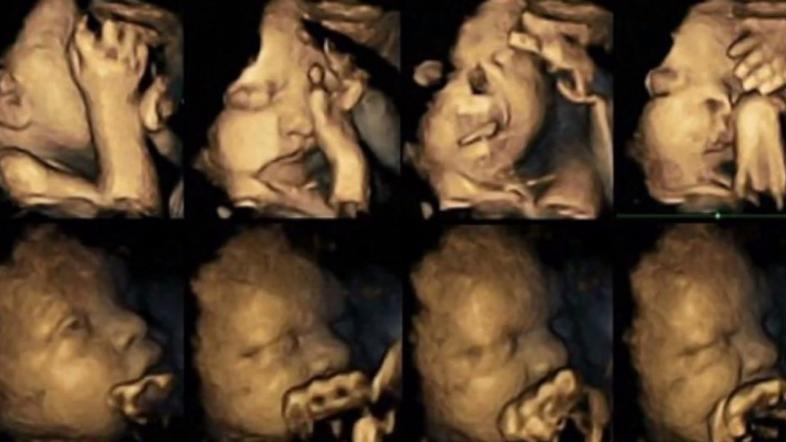

Set fotografij prikazuje plod v maternici matere kadilke (zgoraj) v primerjavi s plodom matere nekadilke (spodaj). Reisslandova je raziskovala gibanje nerojenih otrok s pomočjo ultrazvoka, za primerjavo pa je sledila 20-im nosečnicam. Od tega so bile štiri kadilke. Plod je opazovala pri starosti 24, 28, 32 in 36 tednov ter pri tem posnela na tisoče majcenih premikov.